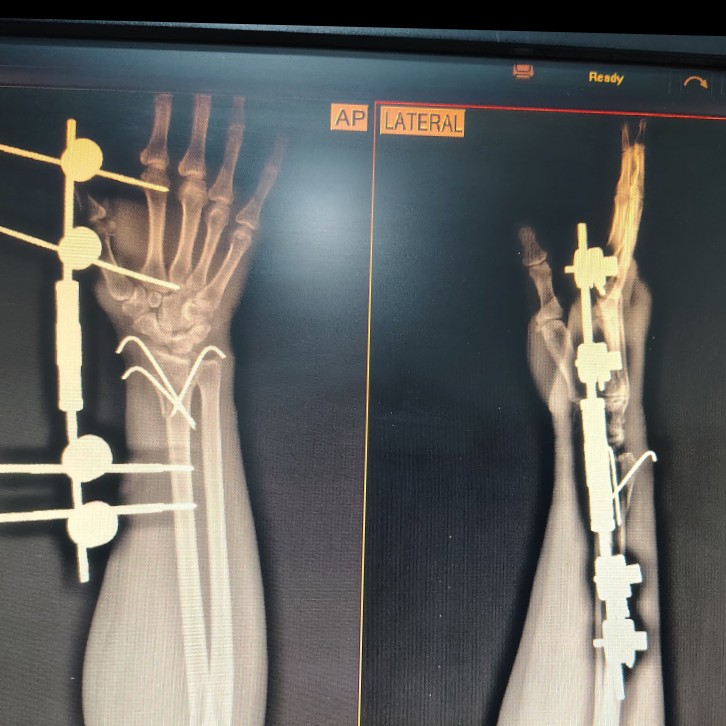

At Soham Orthopaedic and General Health Clinic, we are committed to delivering expert medical care with a patient-centered approach. Led by Dr. Swapnil Shendge and Dr. Kalyani Shendge Chaudhari, our clinic offers specialized treatments in orthopedics, general medicine, nutrition, and skin care to ensure comprehensive healthcare for individuals of all ages.Dr. Swapnil Shendge (MMC 2017041320) is a highly skilled orthopedic surgeon specializing in joint replacement and complex trauma surgeries. With an extensive background in hip, knee, and shoulder replacements, he is passionate about restoring mobility and relieving pain for his patients. His expertise extends to the treatment of fractures...